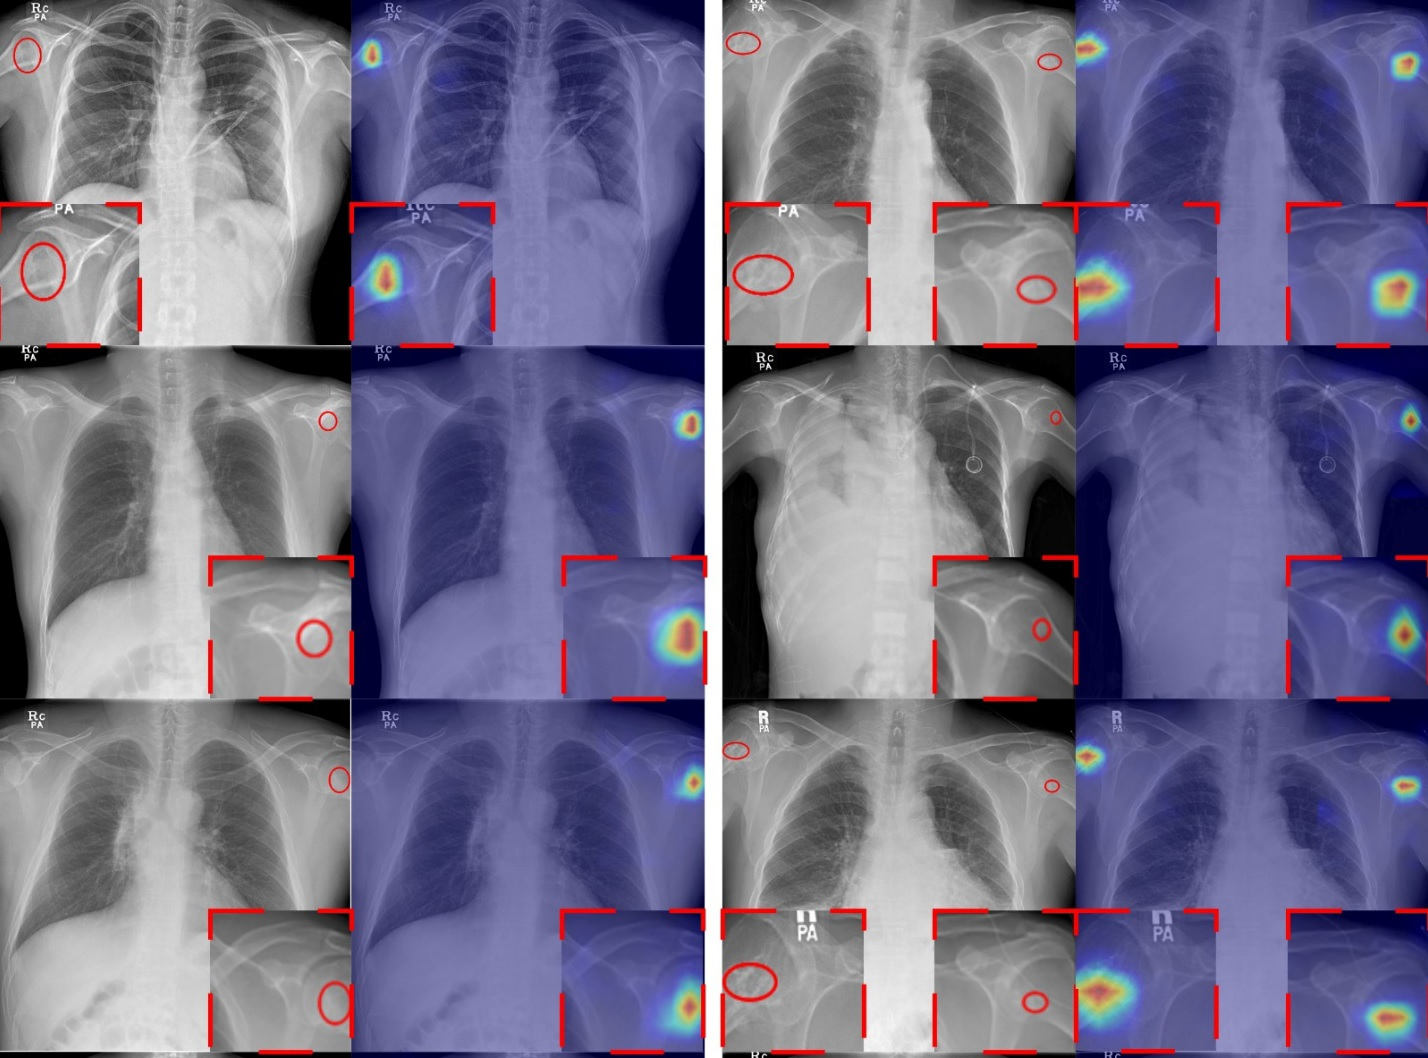

Diagnosis of acute PE tends to be made with a PE-protocol CT pulmonary angiogram (CTPA); preliminary findings from this exam are reported by a radiologist via a free-text report. Previous research has shown that using NLP algorithms with these unstructured reports is more effective for identifying PE than using administrative diagnosis codes, Amin's team explained, so the group developed and validated an NLP-based clinical decision support tool that could automatically flag patients presenting to the emergency department with low-risk PE and thus identify candidates for safe outpatient management.

The study included data from 12,183 individuals who underwent a PE-protocol CTPA in the emergency department between June 2018 and December 2020. Reports from these exams were categorized as positive or negative for PE, then divided into development, internal validation, and temporal validation cohorts to train, test, and validate a natural language processing model that could identify PE based on unstructured text. The investigators gathered risk stratification, patient- and encounter-level data from the electronic health record and used these data to calculate a simplified pulmonary embolism severity (sPESI) score at the time of PE diagnosis.

The team also reported that the natural language processing model performed well when it flagged the presence of PE from a radiology report in the internal and temporal validation cohorts.

| Natural language processing model performance for identifying PE from radiology reports in internal and temporal validation cohorts | |

| Measure | Finding |

| Area under the receiver operating curve | 0.99 |

| Sensitivity | 86% to 87% |

| Specificity | 99% |